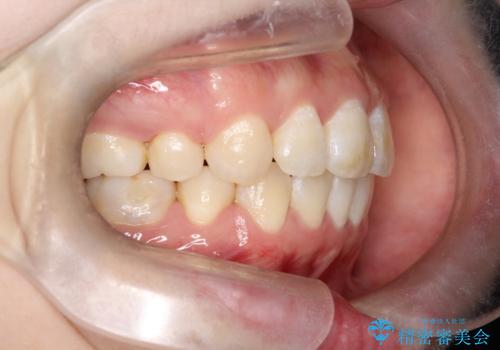

- 矯正装置

- 審美装置

- 治療計画

- ”口元を下げたい”が主訴で来院されました。

抜歯してワイヤー矯正を行い、口元も改善され大変満足していただきました。

小臼歯の抜歯を行うことで口元を改善することができました。